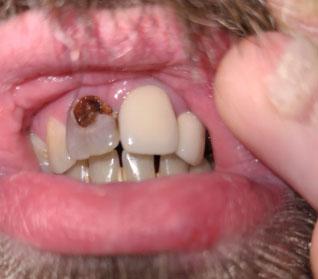

Severe Cervical Decay on Upper Front Tooth – Full Dental Case Analysis (100% Zoom)

The image shows a severely decayed upper front tooth with a dark cavitated lesion at the gum line (cervical/root area). The decay appears deep and irregular, strongly suggesting involvement of dentin and possible pulp exposure. Adjacent teeth appear structurally intact, which is a favorable sign.

This type of damage is commonly associated with long-term acidic beverage intake, high sugar consumption, and prolonged periods of oral hygiene neglect, often linked to depression or systemic health challenges.

Primary Diagnosis

Advanced cervical and root caries on an upper anterior tooth

Possible irreversible pulpitis or early pulp necrosis

Localized gingival inflammation without advanced bone loss